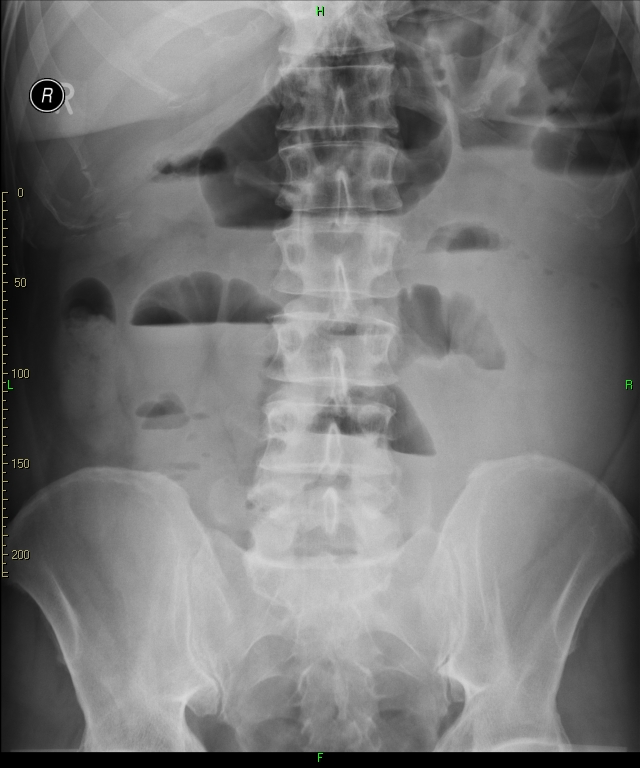

12 A young dancer was partying in the dressing room with his friends. He suddenly swallowed down an object which on the abdominal radiogram proved to be a cupboard key.